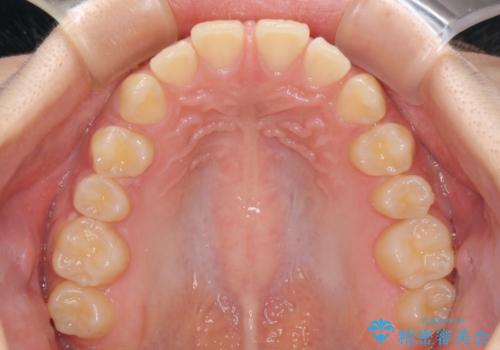

前歯のすきっ歯を治したい インビザラインによる矯正治療

- 上顎前歯の隙間を気にして来院された患者様です。

目立たない装置を希望とのことで、インビザラインを用いて矯正治療を行うこととしました。

最終的には隙間は全て閉じ、綺麗な仕上がりとなりました。